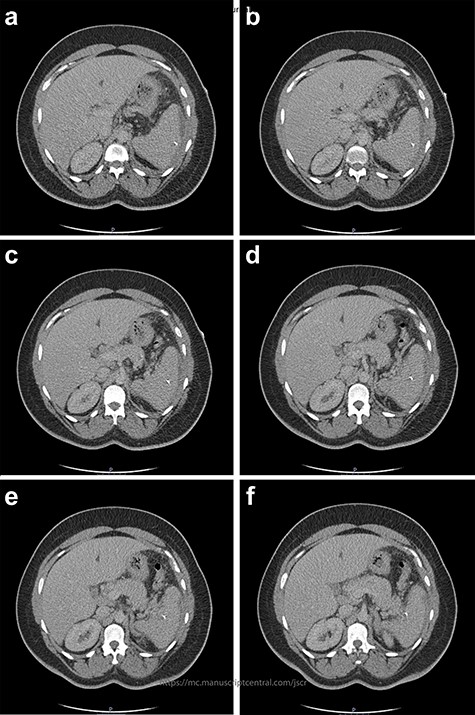

The initial bloods showed haemoglobin 121 g/l, white cell count 29.2x109/l, lactate 0.8 mmol/l, C-reactive protein 348 mmol/l and deranged alkaline phosphatase at 175 mmol/l, with other blood results in normal ranges. A diagnosis of intra-abdominal sepsis secondary to acute cholecystitis was suspected and initial resuscitation was commenced. A computerized tomography (CT) scan of the thorax, abdomen and pelvis demonstrated a mild left pleural effusion with bibasal subsegmental consolidation, splenic subcapsular haematoma, splenic hypodensity and a linear hyperdensity density crossing the upper anterior pole of the spleen, referred to hereafter as the foreign body (Figs 1–3).

Two-mm axial section from a CT scan showing the perisplenic haematoma (*) and hypodensity (arrow) separating the upper anterior pole of the spleen (p) from the body (b). CT section number 54.